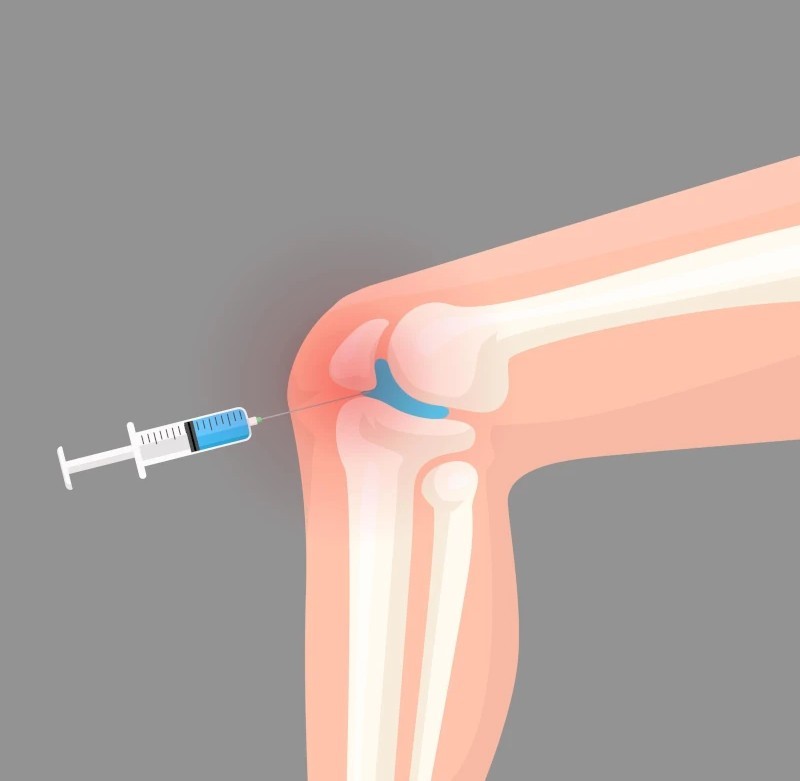

آرتروز زانو یکی از شایعترین بیماریهای مفصلی است که بهویژه در سنین میانسالی و سالمندی بروز میکند. این بیماری به مرور باعث تخریب غضروف مفصل زانو شده و درد، التهاب، خشکی مفصل و محدودیت حرکتی را به دنبال دارد. در بسیاری از موارد، بیماران به دنبال راهی برای کنترل درد هستند که بدون نیاز به جراحی، کیفیت زندگیشان را بهبود بخشد. یکی از مؤثرترین و کمتهاجمیترین روشهای درمانی در سالهای اخیر، تزریق ژل هیالورونیک اسید به داخل مفصل زانو است.

هیالورونیک اسید (Hyaluronic Acid) مادهای طبیعی است که در مایع مفصلی زانو و سایر مفاصل بدن یافت میشود. این ماده باعث روان شدن حرکت مفصل، جذب ضربههای وارده و محافظت از غضروف میشود. با افزایش سن یا در اثر بیماری آرتروز، میزان این ماده در مفصل کاهش مییابد و همین عامل موجب خشکی، درد و تخریب بیشتر مفصل میشود.

تزریق مستقیم هیالورونیک اسید به مفصل زانو، نوعی جایگزینی یا تکمیل مایع مفصلی طبیعی محسوب میشود. این کار باعث کاهش اصطکاک استخوانها، افزایش روانی مفصل و در نهایت کاهش درد و بهبود عملکرد حرکتی میشود.

روند انجام تزریق ژل به زانو چگونه است؟

فرآیند تزریق ژل معمولاً توسط پزشک متخصص طب فیزیکی، ارتوپدی یا روماتولوژی انجام میشود و شامل مراحل زیر است:

- بررسی وضعیت مفصل: قبل از تزریق، پزشک با استفاده از معاینه بالینی یا تصویربرداری (مانند MRI یا سونوگرافی) وضعیت مفصل را ارزیابی میکند.

- ضدعفونی محل تزریق: پوست اطراف مفصل کاملاً استریل میشود تا احتمال عفونت به حداقل برسد.

- تزریق ژل با هدایت دقیق: در برخی موارد، از سونوگرافی برای هدایت دقیق سوزن استفاده میشود تا ژل مستقیماً به داخل فضای مفصل تزریق شود.